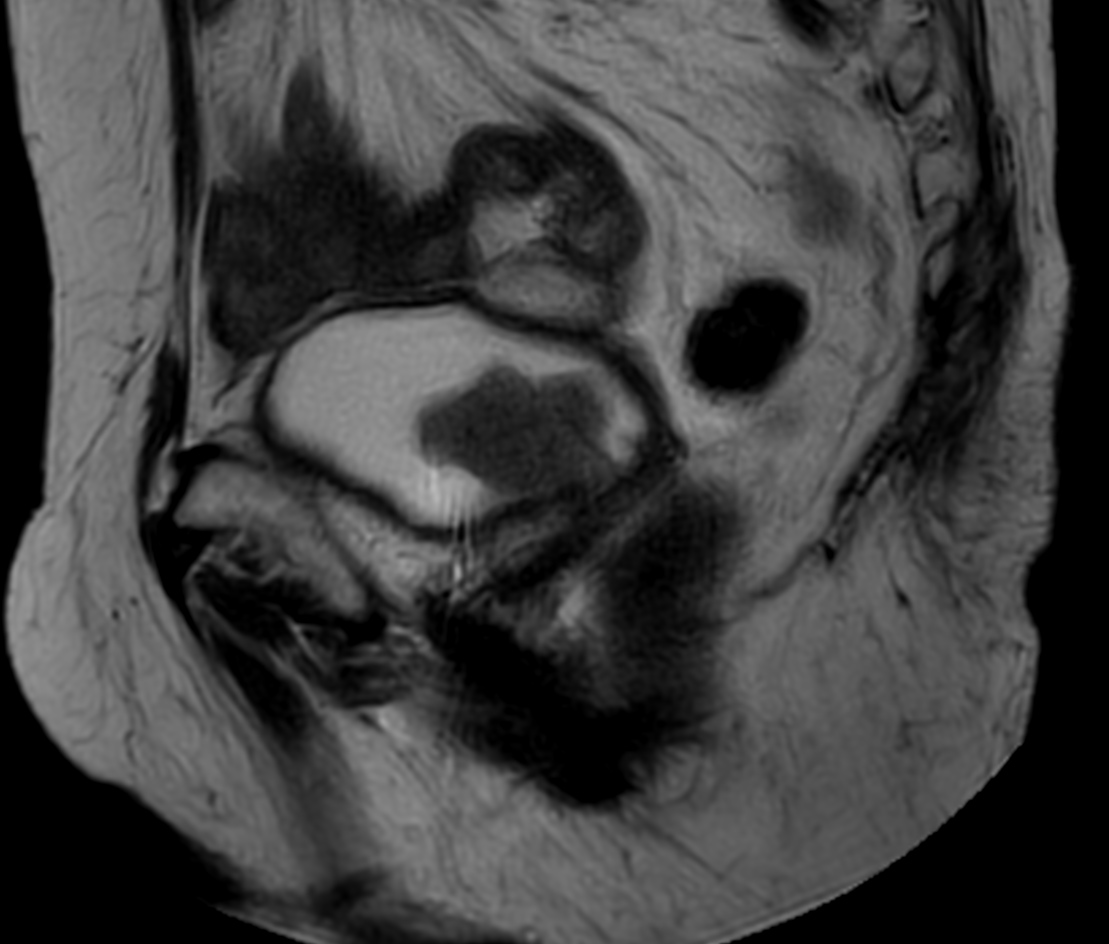

Patient with bladder cancer. The ExamCard includes techniques for motion reduced imaging (MultiVane XD), 3D TSE imaging (PelvisVIEW) allowing for multiple image directions in one single scan, a multi-phase contrast-enhanced sequence (4D FreeBreathing) to improve imaging confidence and Compressed SENSE to accelerate the entire exam.

3D T2w TSE PelvisVIEW Compressed SENSE

3D T2w TSE PelvisVIEW (reformat) Compressed SENSE